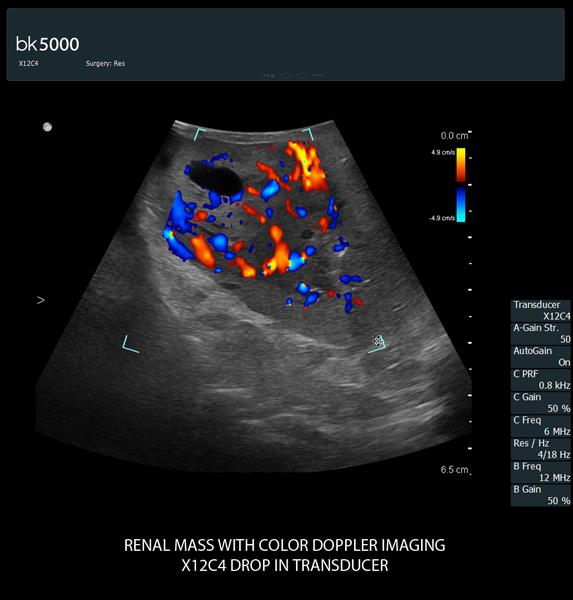

Superb Color Doppler And Unique 3D Visualization

Extremely sensitive color Doppler with superb spatial resolution identifies arterial and venous blood supply to the tumor. This is especially important in procedures where selective clampingis needed. Unsurpassed 3D imaging enables easier identification of key anatomical landmarks and dissection planes.

The unique Drop-In transducer enables access and visualization of complex organs and difficult-to-access anatomy in real-time. For example, in kidney navigation and difficult-to-access endophytic and exophytic tumors, the small, compact, curved linear array Drop-In transducer enables a wider field of view for faster examinations. The specially-designed fin grasped by the robotic arm ensures maximum control and organ contact so you can get the information you need.